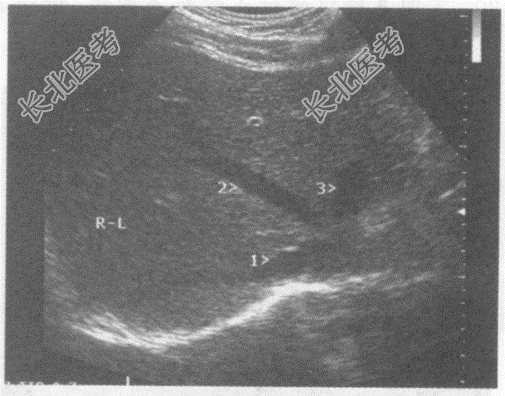

- 单项选择题图中1、2、3所指部位的解剖名称分别为:

A、1-门脉右支、2-肝中静脉、3-门脉左支

B、1-肝右静脉、2-肝中静脉、3-肝左静脉

C、1肝左静脉、2-肝中静脉、3-肝右静脉

D、1-门脉右后支、2-门脉右前支、3-门脉左支

E、1-肝中静脉、2-肝右静脉、3-肝左静脉